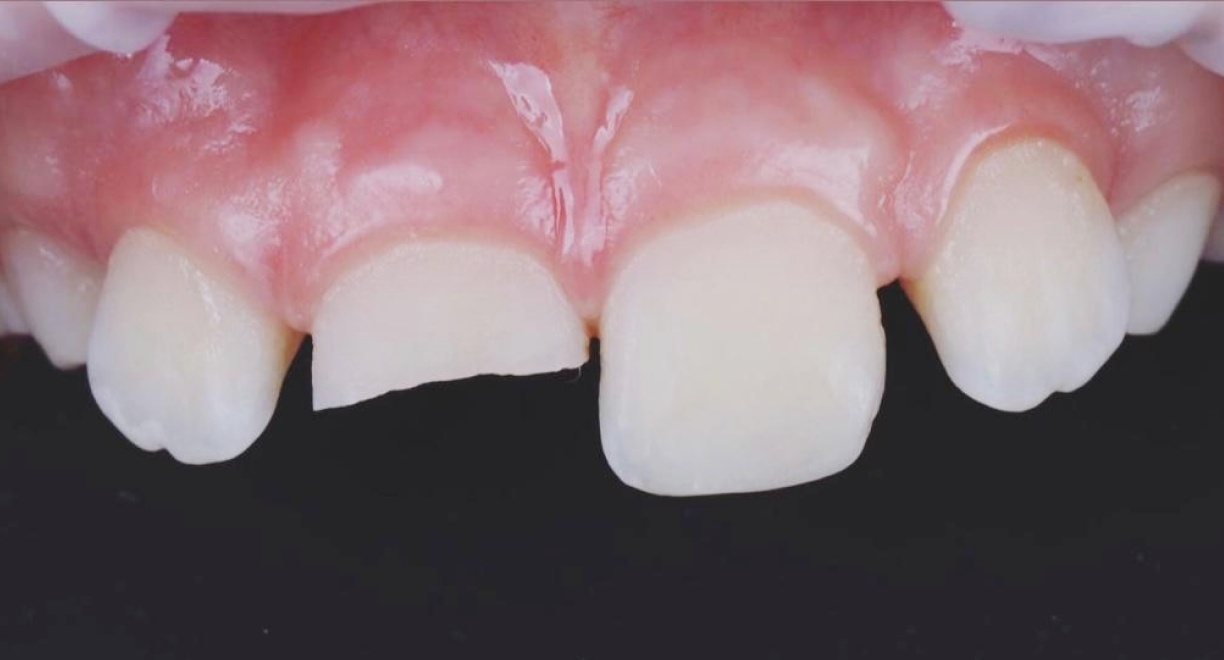

• Tooth Restoration After Trauma

Following a dental injury, the patient received aesthetic and functional restoration of the damaged tooth, carefully recreating its natural shape, colour, and proportions. High-quality composite materials were used to achieve a perfect match with the surrounding teeth and a seamless, natural result. The treatment successfully restored both the appearance and function of the tooth, maintaining the natural beauty of the patient’s smile.

Doctor: Anna Petrova